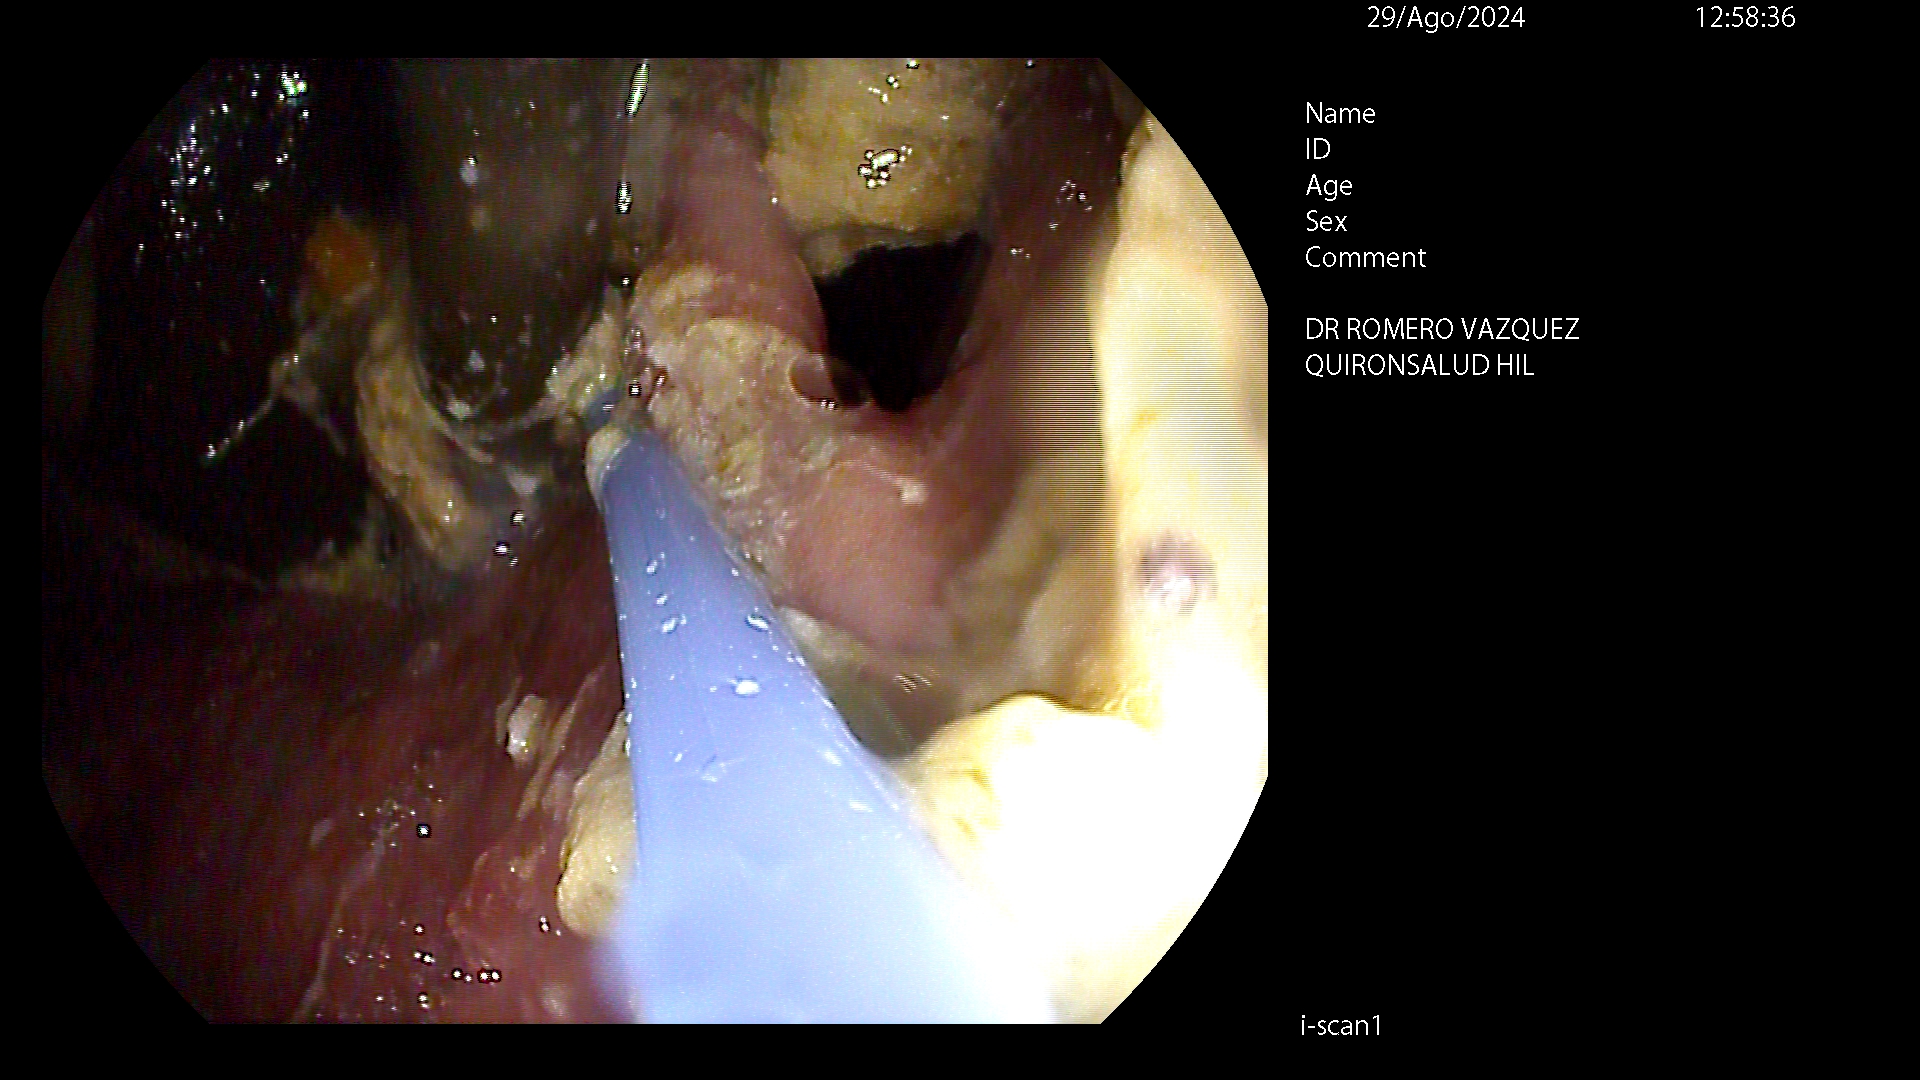

ENDOMANGA

La endomanga es una técnica quirúrgica (gastroplastia) mínimamente invasiva que se realiza por vía endoscópica, es decir, a través de la boca y que permite modificar de forma definitiva la forma del estómago, acortándolo e igualmente dándole un aspecto pseudo-tubular. No se realizan incisiones externas y, por tanto, no hay cicatrices. Está indicada como primera opción para pacientes con obesidad moderada (IMC entre 30 y 40), o en caso de obesidades severas (IMC superior a 40) que no desean enfrentarse a técnicas quirúrgicas de mayor envergadura (cirugía bariátrica) para reducción del peso.

El objetivo de la endomanga gástrica es reducir el estómago, limitando la capacidad de éste. Como consecuencia de ello, el paciente presenta una mayor saciedad ingiriendo una menor cantidad de alimentos y le es más fácil adaptarse a nuevos hábitos saludables duraderos.

La gastroplastia endoscópica mediante la técnica endomanga se realiza por el gastroscopia, bajo anestesia general y dura aproximadamente entre 25 y 35 minutos. Mediante la endoscopia se realizan unos 18 pliegues definitivos a lo largo de todo el cuerpo gástrico, reduciendo de manera importante su capacidad de apertura, acortándolo y estrechándolo. Gracias a esta reducción los pacientes disminuyen la sensación de hambre.